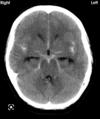

What does the CT depcit? Epidural haematoma Subarachnoid haematoma Subdural haematoma Intracranial haematoma

What does the CT depcit? Epidural haematoma **Subarachnoid haematoma** Subdural haematoma Intracranial haematoma